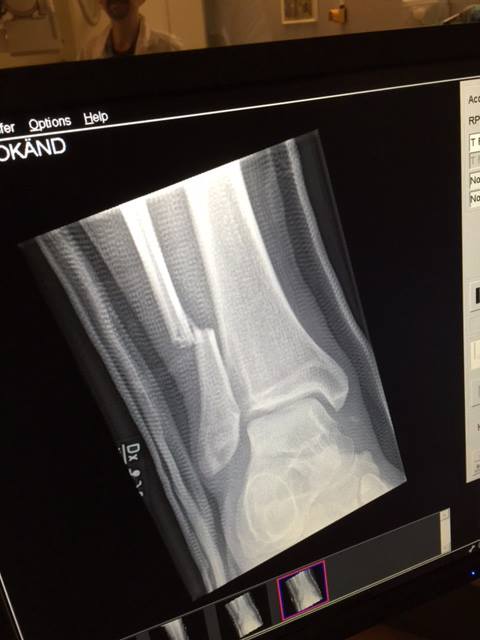

La banda compartió radiografía una vez finalizado su show en Suecia.

En vez de cancelar el show, Grohl se tomó un momento para ser atendido por urgencias y volver en camilla al escenario para terminar el show. Una vez concluido el set, la banda compartió foto de la radiografía a la pierna de su líder, donde se puede apreciar la dimensión del accidente.